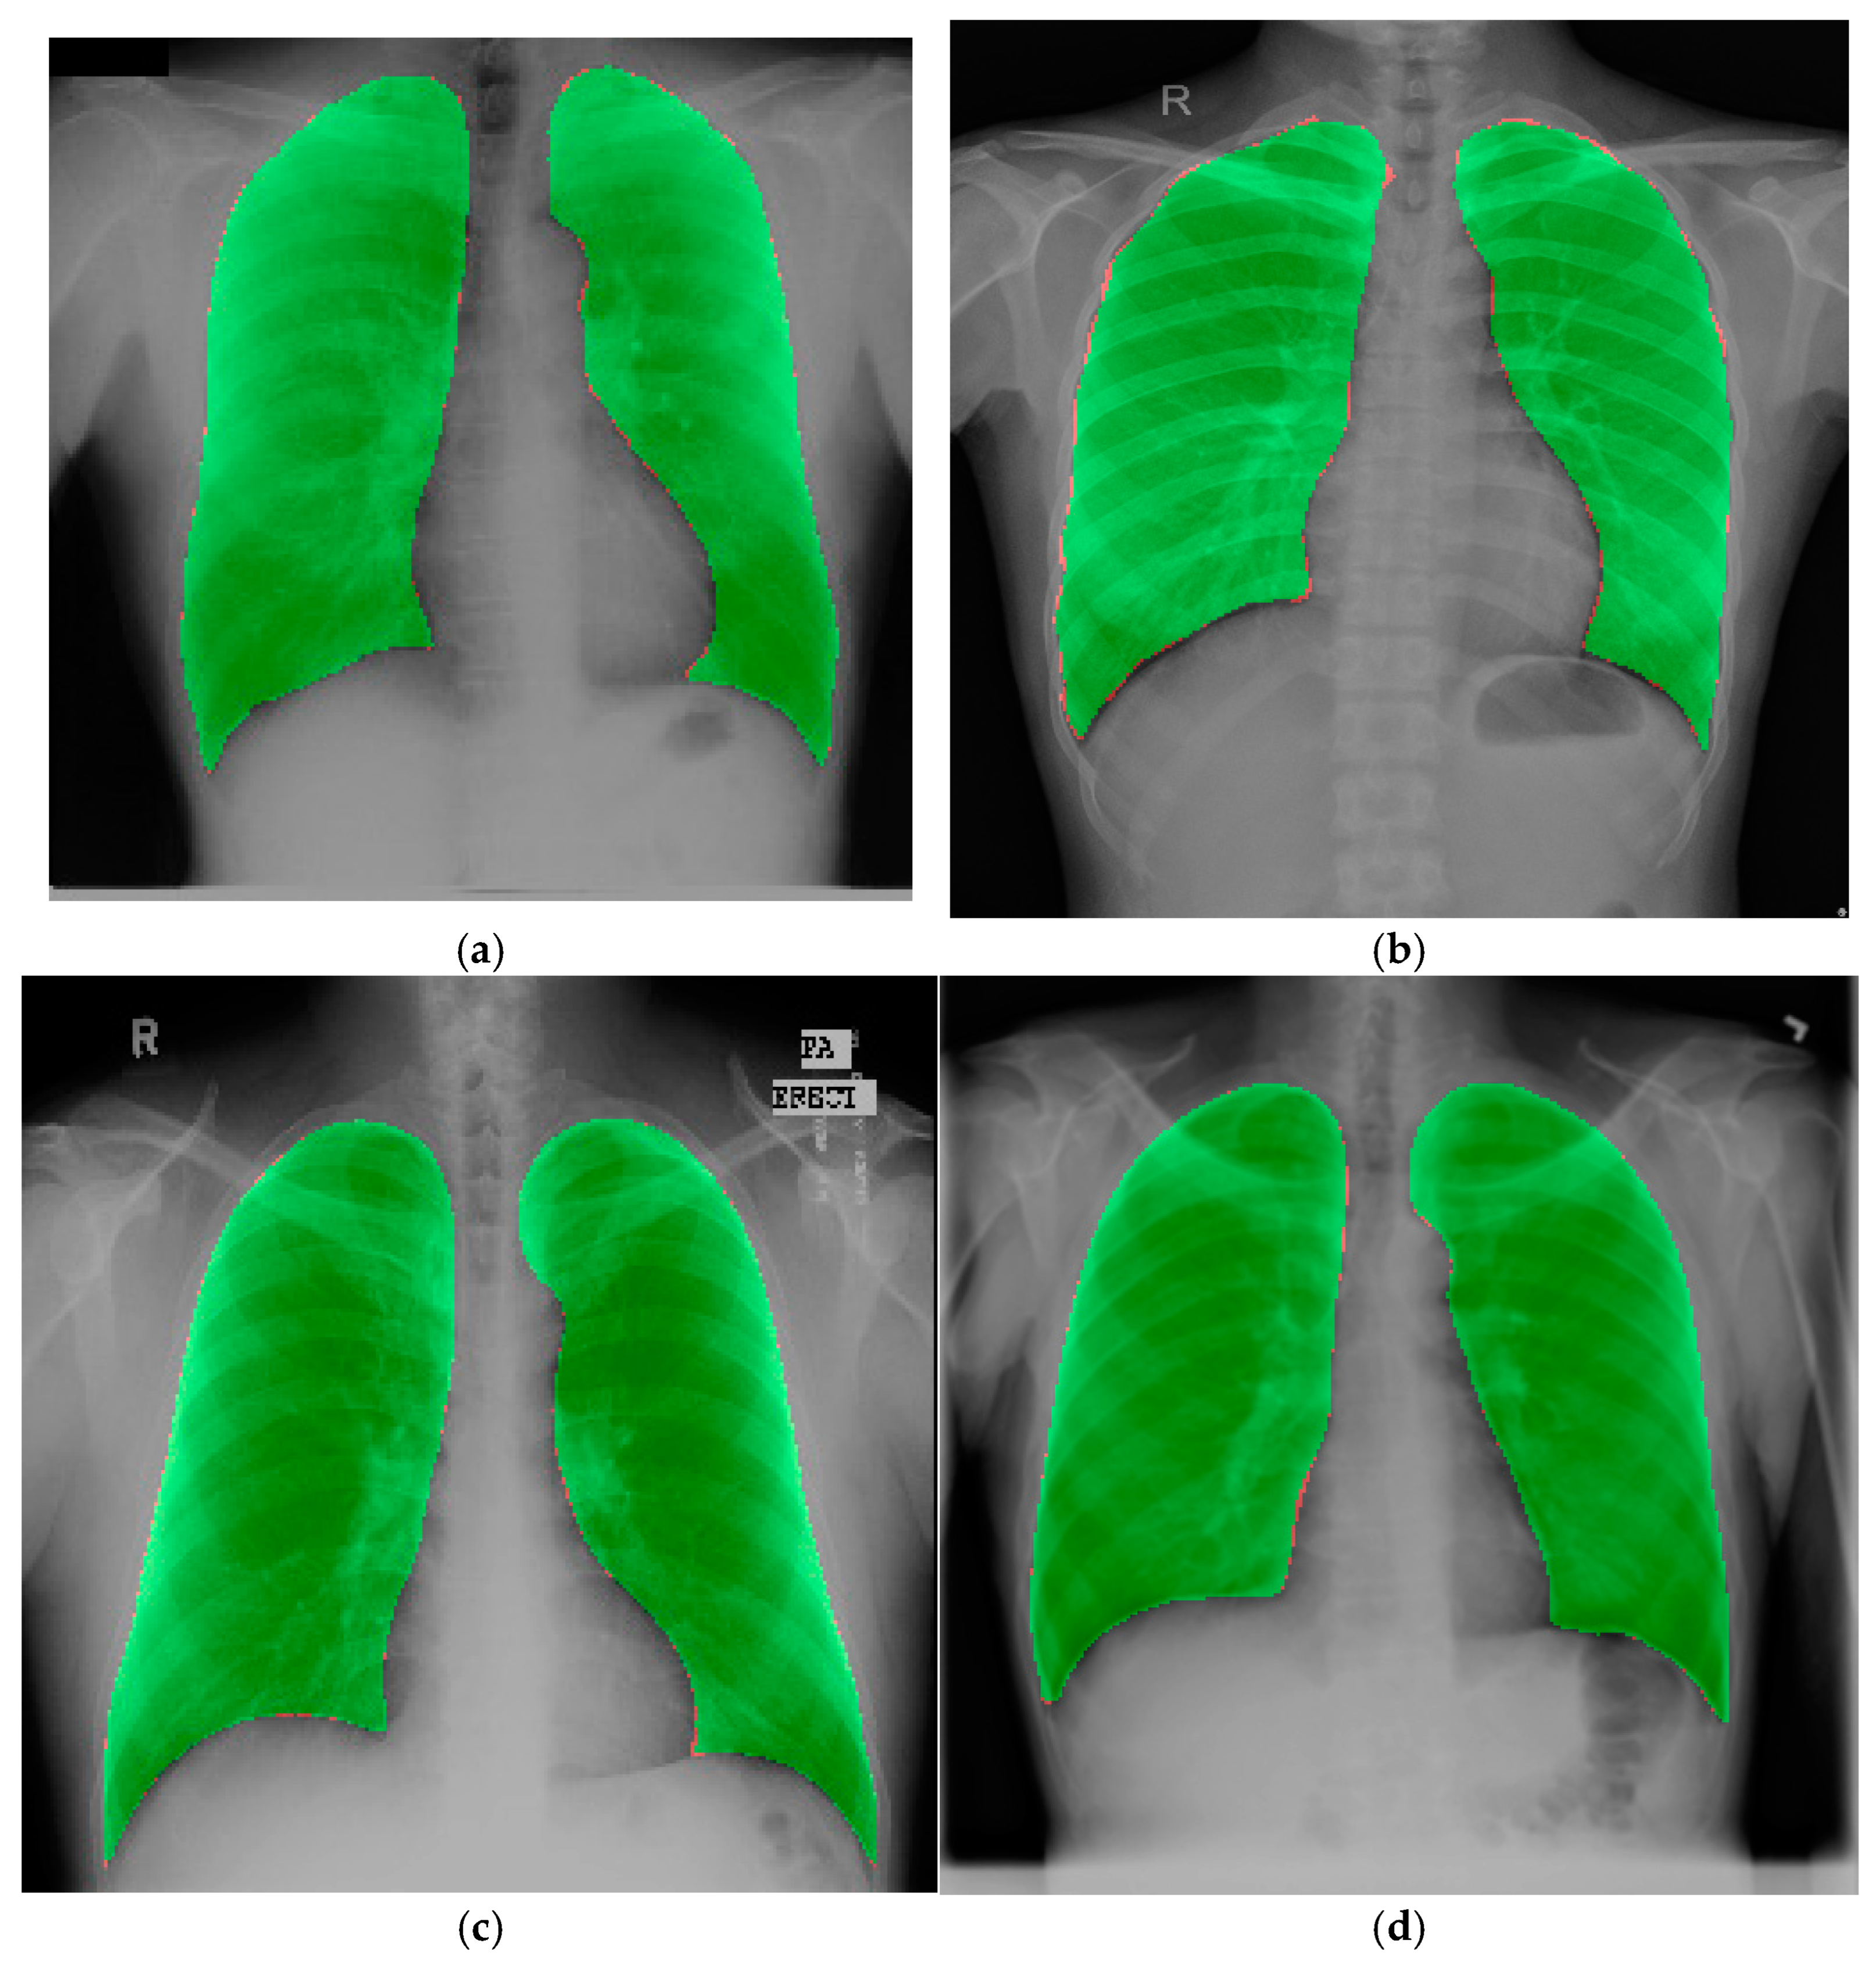

4.3. Experimental Results on the Chest X-Ray Dataset for External Validation

- The effectiveness of the model was examined on three different popular datasets (JSRT, SZ, and MC), where it outperformed all other SOTA models.

- A random chest X-ray dataset from Kaggle was used for external validation, demonstrating the model’s effectiveness and robustness.